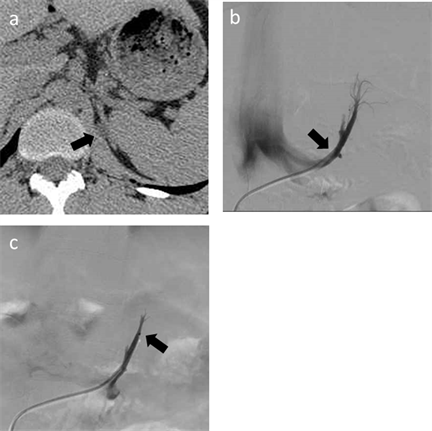

A 5.2-Fr reverse-curve catheter (Simons Shaped Carry; UTM, Aichi, Japan) was inserted into the left adrenal vein and venography was performed. In all patients, the left adrenal vein was found with the inferior phrenic vein. Blood samples were collected in the central adrenal vein (CAV) and the common trunk vein (CTV), which are above and below the inferior phrenic vein, respectively. When the blood sample was obtained from CAV, a microcatheter (2.7Fr Carry High-flow, UTM, Aichi, Japan or 2.8Fr Renegade Hi-Flo, Boston Scientific Corporation, Natick, MA, USA) was inserted through the orifice of the inferior phrenic vein (Figure 1).

Figure 1. A 25-year-old man with primary aldsteronism (patient 54). Endocrinologists evaluated the parameters and determined that only left adrenal gland was involved. This patient underwent adrenalectomy, and histological analysis confirmed the adrenal adenoma. (a) Axial CT image with 1.25 mm slice thickness demonstrating a low-density nodule in the left adrenal gland (arrow). (b) Venogram of the common trunk of the left adrenal vein. A blood sample was obtained via a 5.2-Fr catheter in the common trunk vein (arrow). (c) A microcatheter was inserted through the confluence of the inferior phrenic vein, and a blood sample was obtained via the microcatheter (arrow).